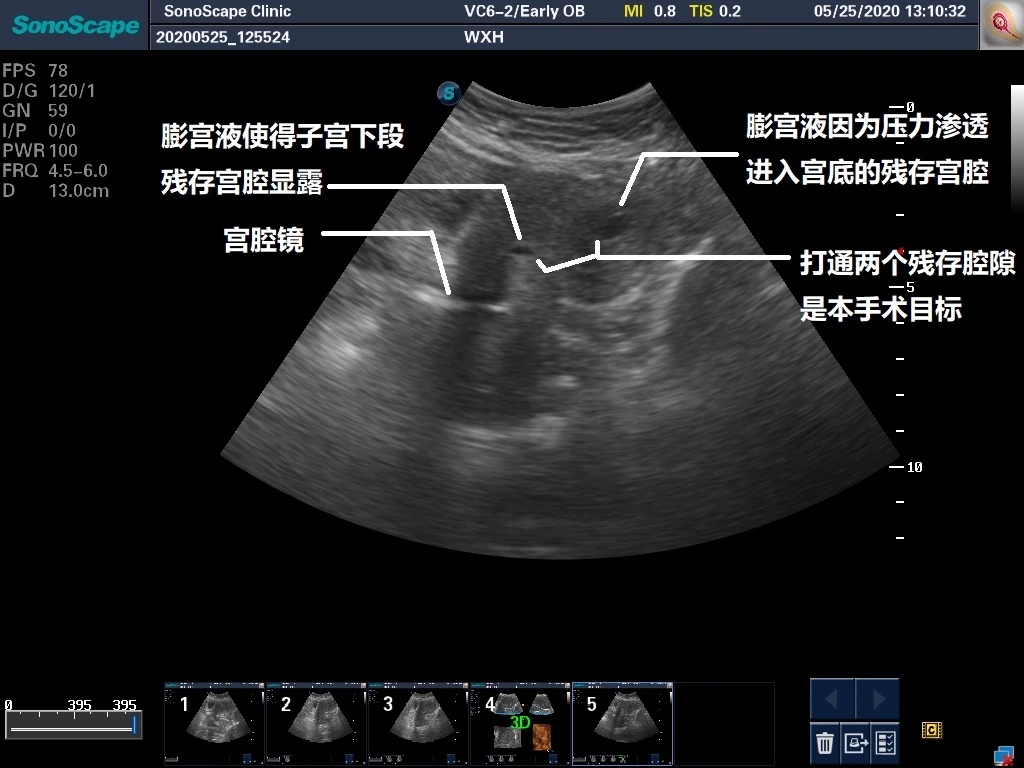

在这个超声上面,悍然出现两个“眼睛”,彩超见原“内膜仅存之处”呈现一个被膨宫液撑起的腔,而与宫腔镜末端紧邻之处则也呈现出一个腔隙,那个就是我们宫腔镜下所看到的小空间。将两个腔隙之间的部分打通,即可恢复宫腔结构。上图进行辅助线标记如下:

得益于彩超的方向引导,我们这么做:使用小剪刀在彩超监视下从宫颈内口的腔向宫底部的腔进行“进攻”,行程过半后,直接使用宫腔镜镜体沿着刚才操作形成的通道进行钝性分离,直达宫底部腔隙。以下视频展现的是分离过程以及宫腔镜进入宫底部腔隙之后所看到的内膜情况。